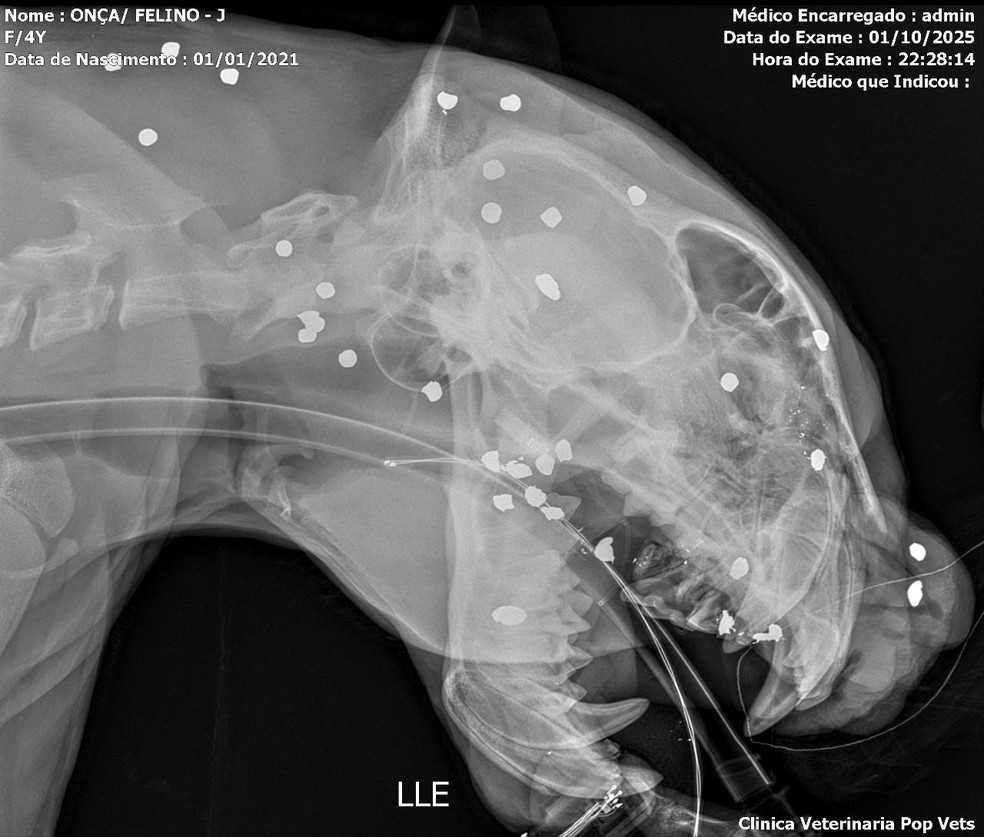

Um exame de raio-X realizado após o resgate de uma onça-pintada no Rio Negro, em Manaus, revelou que o animal foi atingido por mais de 30 estilhaços de tiro distribuídos pelo rosto, cabeça e pescoço. O resgate ocorreu na quarta-feira (1º) após o felino ser visto nadando por horas, aparentemente desnorteado, em direção à Praia da Ponta Negra, na Zona Oeste da capital amazonense.

De acordo com a equipe veterinária responsável pelo atendimento, além dos estilhaços, o animal apresentava dentes quebrados, ferimentos visíveis na cabeça e debilidade intensa. Segundo o biólogo e pesquisador em felinos Rogério Fonseca, os tiros parecem ter sido disparados à distância, possivelmente com a intenção de afugentar o animal, já que tiros concentrados na região do rosto teriam levado à morte imediata.